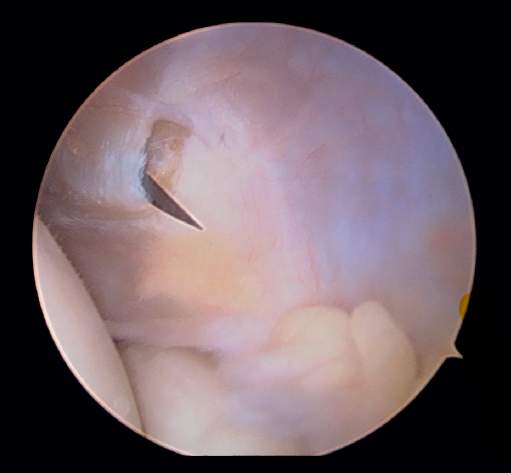

En primer lugar, se realiza el portal anteromedial de visión, incidiendo únicamente la piel y realizando disección roma con un mosquito recto. A continuación, se introduce la vaina del artroscopio, atravesando de forma anterior y proximal el septo fibromuscular medial, en dirección a la cabeza del radio, de forma posterior y distal, para evitar lesionar el nervio cubital y el paquete vascular anterior del codo. Una vez introducida la óptica en el portal medial, se procede a realizar el portal lateral proximal como portal de trabajo. Se realiza bajo visión directa, utilizando como guía una aguja intramuscular de fuera a dentro, para localizar el punto de entrada que permita mejor ángulo de trabajo (Figura 4). Posteriormente, se incide en la piel y se realiza disección roma con un mosquito recto para entrar en la articulación (Figura 5).

Figura 4. Posicionamiento con aguja del portal lateral (paciente en decúbito lateral, codo derecho, visión desde el portal medial).